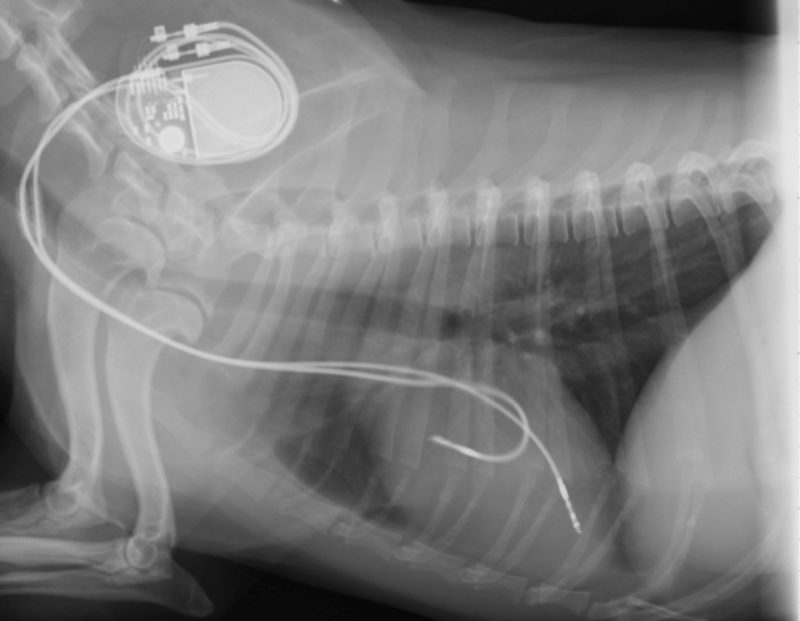

Nachdem weitere notwendige Voruntersuchungen (Röntgenbilder des Brustkorbes, ein Herzultraschall, Blutdruckmessung sowie Blutuntersuchungen), die dem Zweck dienen zusätzliche Erkrankungen oder Folgeerscheinungen des AV-Blockes III Grades aufzudecken, durchgeführt worden waren, stellte sich „Jackson" als guter Kandidat für diesen Eingriff dar. Auf Grund des lebensbedrohlichen Charakters der Rhythmusstörung wurde der Eingriff umgehend vorgenommen. Bei einer Herzschrittmacherimplantation werden mit Hilfe von Schrittmachersonden, welche i.d.R. über das Gefäßsystem eingebracht und unter Röntgendurchleuchtung bis ins Herz geschoben und dort verankert werden, neue elektrische Impulse („Pacing“/Stimulation) an die Stellen gebracht die durch den AV-Block abgeschnitten wurden. Hierdurch kann dann wieder eine normale Herzfrequenz erreicht werden. Es werden hierbei verschiedene System insbesondere ein 1-Kammer und ein 2-Kammer-System.

Bei einem Zweikammersystem wird eine Sonde in die rechte Vorkammer (Atrium) und eine zweite Schrittmachersonde in die rechte Hauptkammer (Ventrikel). Beide Sonden werden mit dem „Schrittmacherkästchen“ (Impulsgenerator), welcher die Batterie und das Verarbeitungszentrum enthält, verbunden. Der Impulsgenerator wird anschließend unter der Haut am Hals vor dem Schulterblatt fixiert. Vorteil dieses Systems ist das die Vorhofsonde die normalen Impulse des Sinusknotens erkennen kann (Sensing) und diese Information anschließend an die Kammersonde weiterleitet worauf koordiniert zu diesem körpereigenen Impuls eine Stimulation (Pacing) des Ventrikels erfolgt. Elektrisch gesehen wird so der AV-Block III Grades überbrückt und es dem Hund zusätzlich ermöglicht sich je nach Bedarf des Körpers mit einer entsprechenden Herzfrequenz an die Situation wie ein normaler Hund anzupassen (Physiologisches Pacing).

Einen sehr kritischen Moment bei einer Schrittmacherimplantation stellt die Einleitung der Vollnarkose dar, da zu diesem Zeitpunkt die ohnehin schon langsame Herzfrequenz weiter absinken kann. Mit Hilfe von intravenösen Medikamenten und eventuell einem temporären Herzschrittmacher wird versucht, den Patient zu stabilisieren. Bei „Jackson“ konnte der 2-Kammer-Schrittmacher erfolgreich implantiert werden. Um eine dauerhafte Überwachung nach dem Eingriff zu gewährleisten wurde der Hund über Nacht auf die Intensivstation verbracht.